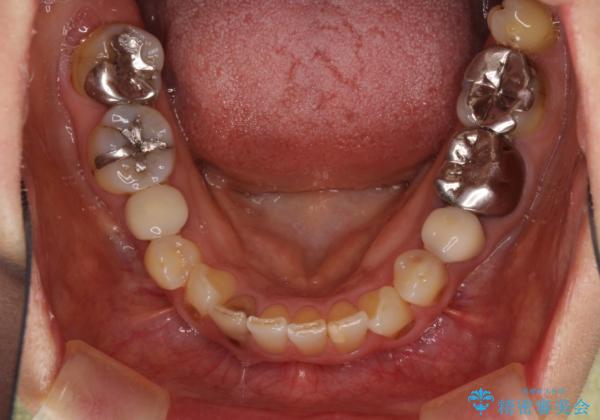

- 目立つ銀歯を気にして来院された患者様です。

奥歯を中心に銀歯が多く装着されており、一部の歯は咬合時に痛みを感じている状態でした。

必要な歯に根管治療を行い、オールセラミッククラウンにて補綴治療を行うこととしました。

一部根管治療では症状が改善しなかったため、歯根端切除術を行いました。